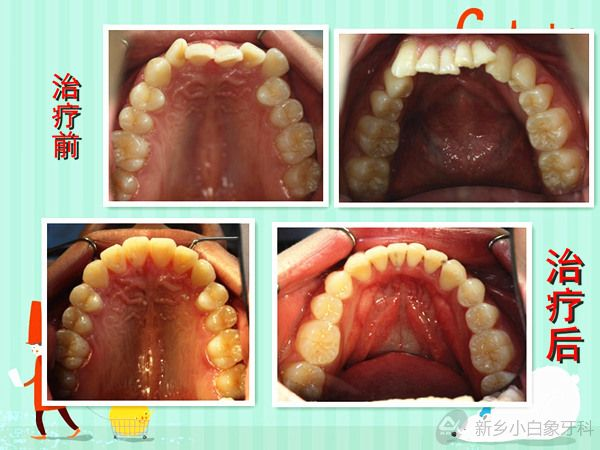

发布时间: 2014-06-27      患者李某某, 男,因“牙不齐、影响美观”来院治疗。初诊时间2011年7月4日,结束时间2014年5月1日。 接诊医生:李呈遥 患者非常满意,现将病例做一回顾性展示:

患者李某某, 男,因“牙不齐、影响美观”来院治疗。初诊时间2011年7月4日,结束时间2014年5月1日。

接诊医生:李呈遥

患者非常满意,现将病例做一回顾性展示: